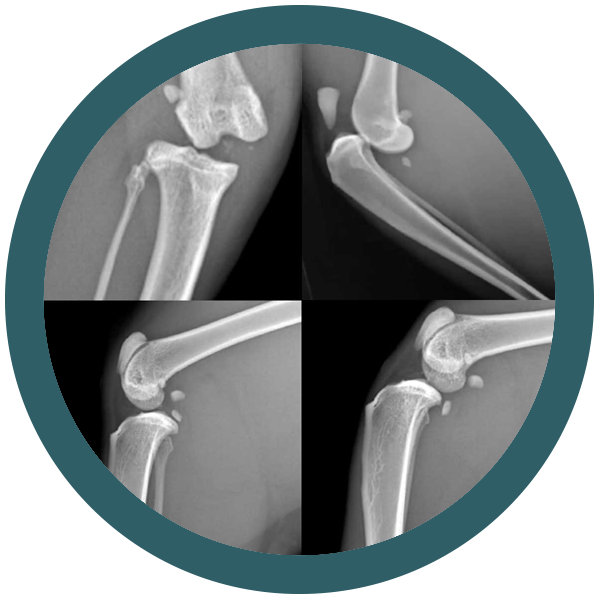

Il tuo gatto è un compagno fedele e amorevole che ti dà gioia ogni giorno. Ma anche i gatti possono soffrire di problemi ortopedici.

La buona notizia è che ci sono molti modi per prevenire i problemi ortopedici nei gatti. Una dieta sana e nutriente, esercizio fisico quotidiano e controlli regolari dal veterinario possono aiutare a mantenere il tuo gatto in forma e sano. Ma cosa succede se il tuo gatto ha un problema ortopedico? In questo caso interveniamo noi di Ortovet.

Siamo una rete di specialisti ortopedici veterinari e offriamo un servizio di elevata qualità, con l’utilizzo delle tecniche chirurgiche più avanzate. I nostri medici veterinari sono esperti nel trattamento di una vasta gamma di problemi ortopedici nei gatti

Quando portarci il tuo animale domestico

Come riconoscere una displasia dell’anca nel gatto